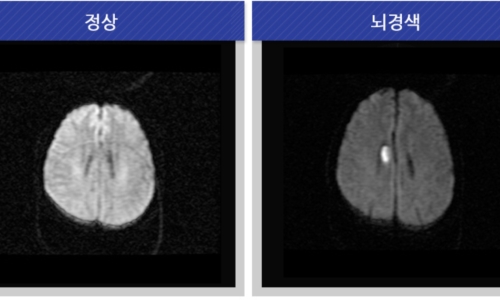

신체가 건강해도 뇌에 문제가 생기게 되면 신체 기능을 제대로 할 수가 없게 됩니다. 뇌 손상으로 제한된 신체 기능은 치료를 마친 후에도 회복이 제대로 되지 않거나 장애로 남는 경우가 많은데 뇌조직이 괴사되며 발생하게 되는 뇌경색이 대표적입니다. 과거에는 뇌출혈 환자가 많았지만 현재는 전체 뇌졸중 환자의 약 60~70%가 뇌경색 환자인 만큼 뇌졸중에서도 뇌경색이 차지하는 비중이 크다고 합니다.

건강보험심사평가원 자료에 따르면 뇌출혈로 병원을 찾은 환자보다 뇌경색으로 내원한 환자가 5배 이상 많았다고 하는데요 뇌경색은 뇌로 통하는 혈관이 막히면서 뇌 조직이 점차 괴사하게 되는 질환으로 날씨가 추워지는 겨울철에 특히 발생 가능성이 높은데요 혈관이 수축 하게 되면서 혈압 상승으로 이어지면서 뇌혈관 질환이 발생하게 되기 때문입니다.